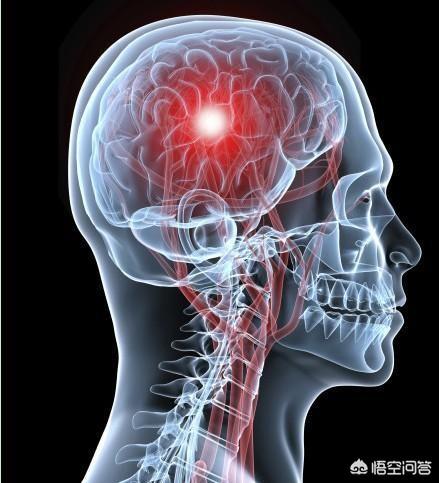

脳梗塞は脳血管障害の一種であり、専門的には「虚血性脳卒中」と呼ばれる。脳血栓症以外にも心房細動などの原因もあります。簡単に言えば、脳梗塞にはいろいろな原因があるが、その中で最も多いのが脳血栓症である。そして、このような脳血栓症の脳梗塞はアテローム性動脈硬化病変、すなわち病理学的基盤がアテローム性プラークに基づくものである。

そして、アテローム性動脈硬化プラークは一般的な慢性病変であり、その発生と発症は高血圧、糖尿病、高脂血症などの多くの要因に影響される。長期にわたる高血圧、高血糖、高脂血症を管理しないと、人体各部の動脈に動脈硬化性プラークが発生しやすくなり、この動脈硬化性プラークが脳動脈に発生すると、脳血栓症発生の下地を作ることになる。たとえば、時間の経過とともに、血圧、血糖、血中脂質がまだコントロールされていない、アテローム性プラークがますます大きくなり、ますます不安定になり、この時、アテローム性プラークが大きくなりすぎたり、突然破裂したりすると、その場で血栓症が発生し、動脈血管が閉塞し、脳梗塞も発生する。

脳血栓症は、実際には脳梗塞の一種であり、脳梗塞の最も一般的な病態である。脳梗塞の多くは、様々な原因(動脈硬化、動脈炎など)により、脳動脈の主幹または一部の皮質枝の内腔が狭窄、あるいは閉塞し、二次的に局所的な血栓が形成され、その結果、脳組織が虚血や壊死を起こし、それに対応する症状や徴候が出現するものである。

1.脳梗塞と脳血栓症の違い:脳梗塞は、脳梗塞、虚血性脳梗塞とも呼ばれ、脳卒中の一種で、最も一般的な脳血管疾患であり、様々な原因で脳血管が閉塞し、脳組織内の血液と酸素が不足して脳組織が壊死し、一連の重篤な症状が現れます。脳血栓症は脳梗塞の一種で、これも脳血管の閉塞が原因である。アテローム性動脈硬化症血管の肥厚、内腔の狭窄および閉塞、血栓症によって形成される。

脳梗塞、脳梗塞、虚血性脳卒中とも呼ばれ、脳の血液循環の障害、虚血、脳組織の局所的な虚血壊死や軟化による低酸素症、それに対応する症状や徴候を指す。

本当の名称は「動脈硬化性血栓性脳梗塞」といい、脳梗塞の中で最も多いタイプである。脳梗塞は、脳動脈硬化を基盤とするプラークが破裂・潰瘍化し、血管の血栓・閉塞が促進されることによって起こる脳組織の局所的な虚血・低酸素状態を指す。